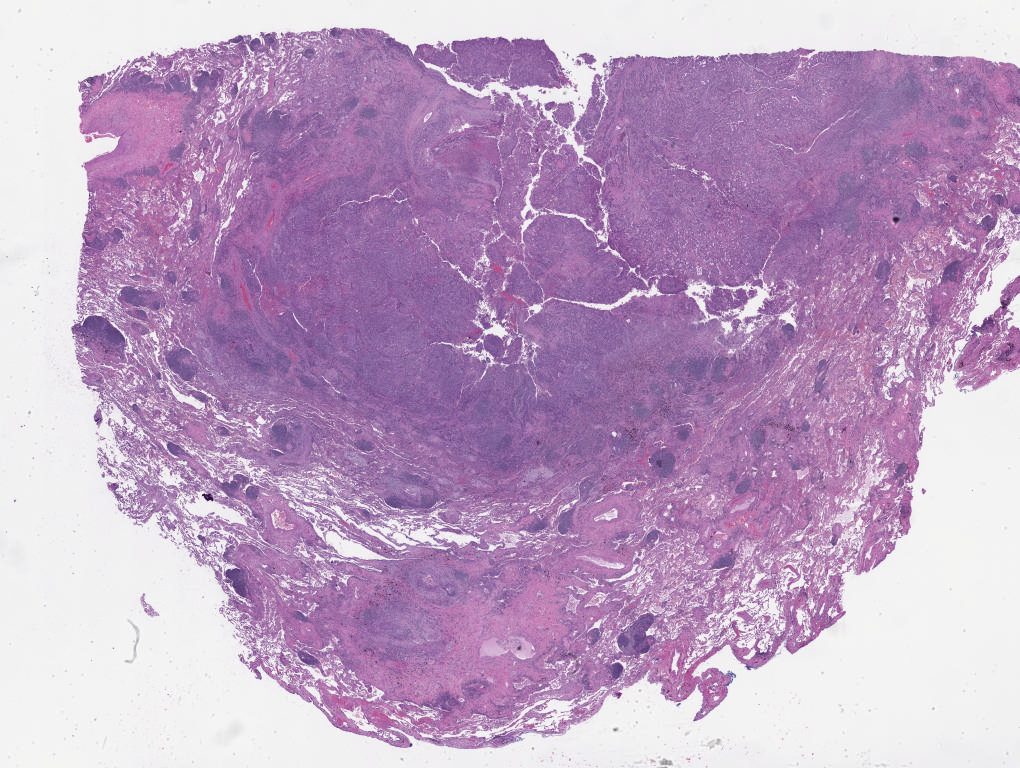

Patient 4.svs

35856

x

28740

@

20X